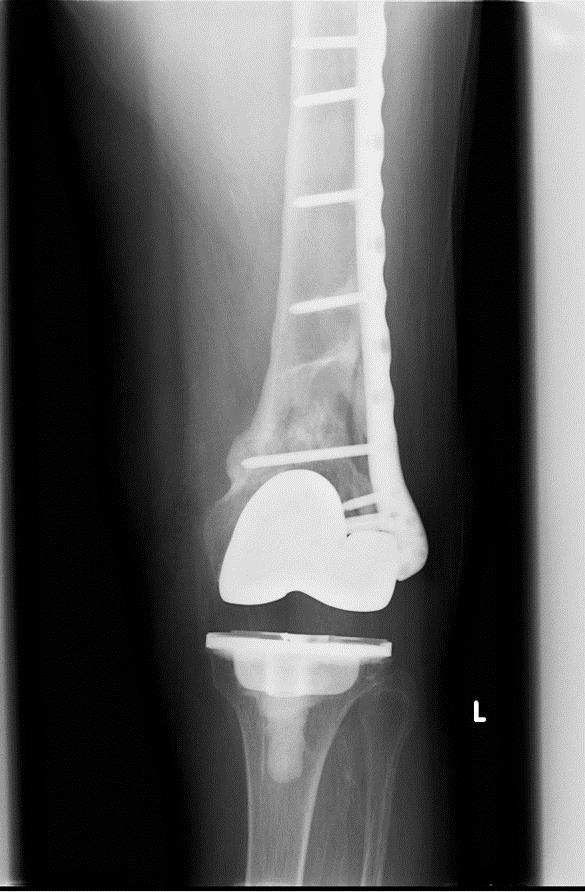

TKA Periprosthetic Fracture Recon Orthobullets Locking Knee Orthobullets Learn about meniscus tear, a knee injury caused by meniscal tears, categorized into two types: A mechanical cause of the locked knee can be identified consistently using three key components from the history and examination:. Find out the clinical definition, presentation,. Find out how to diagnose it clinically with lachman's test. Learn about acl tear, a common athletic injury that. Locking Knee Orthobullets.

From www.orthobullets.com